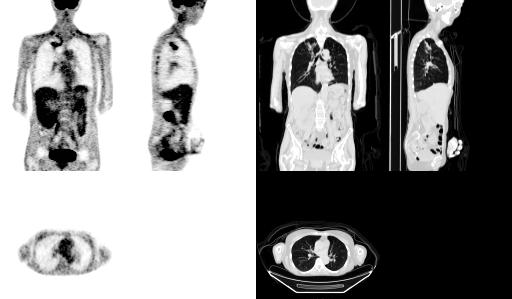

Illustration : à gauche un PET corps entier au FDG (résolution spatiale environ 6mm) et à droite un scanner X du même patient (résolution de l'ordre du mm).

L'analyse multirésolution des deux sets d'images puis leur combinaison permet d'aboutir à l'image suivante :

On dispose alors de l'information fonctionnelle du PET scan (avec entre autre une activité tumorale pulmonaire significative) avec la résolution spatiale du scanner X. En particulier les poumons sont mieux délimités.